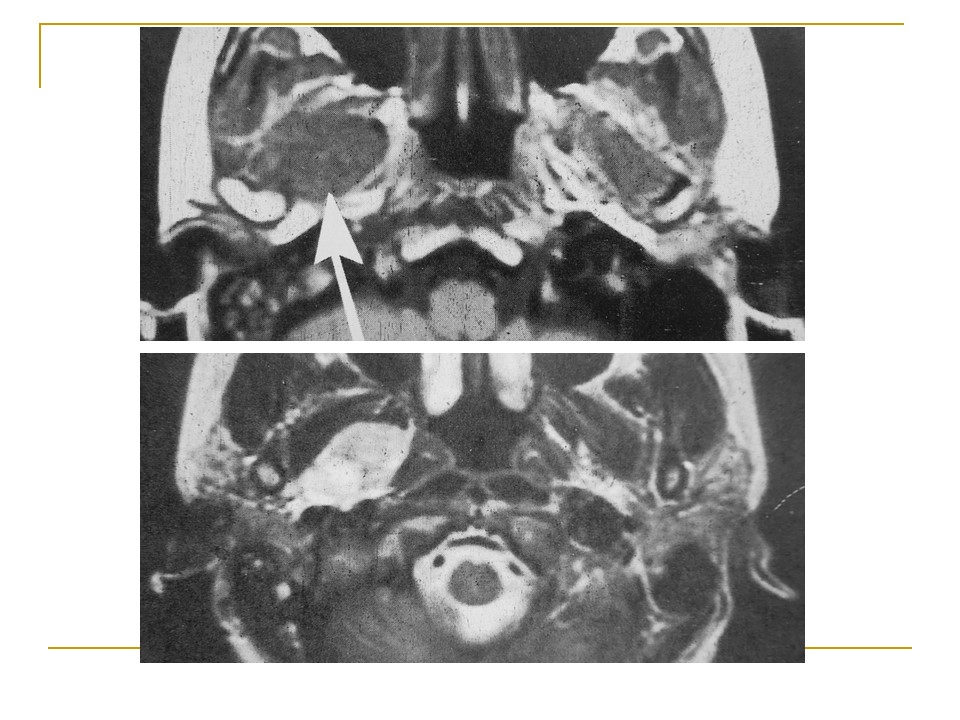

【PPT】鼻腔鼻窦肿瘤与肿瘤样病变的影像学诊断